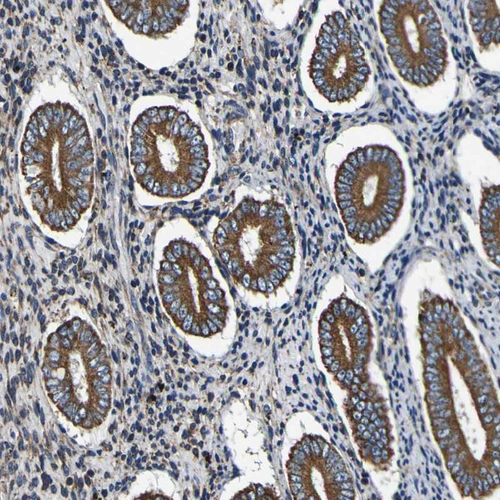

Immunohistochemistry analysis in human endometrium and tonsil tissues using HPA012285 antibody. Corresponding INPP5A RNA-seq data are presented for the same tissues.